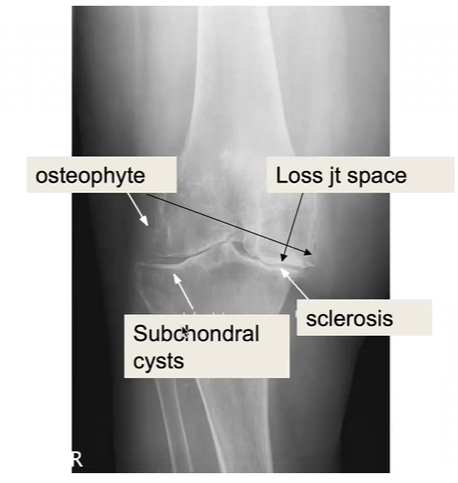

What are the features and pathology depicted

rheumatoid arthritis

features on x-ray (LESS)

also may see deformity + deviations e.g. ulnar deviation